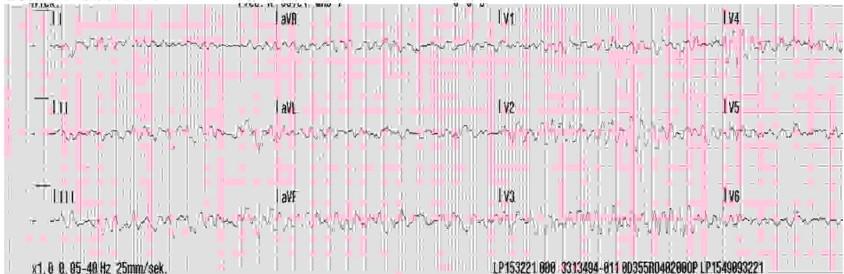

80-letni mężczyzna z kołataniem serca od godziny. Jaką arytmię należy rozpoznać na podstawie zamieszczonego poniżej EKG (przesuw 25 mm/s)?

U 55-letniej kobiety wystąpił ból w klatce piersiowej od godziny. Pacjentka do tej pory czuła się dobrze. Ból wystąpił dość nagle, ale początkowo był słaby, nasilił się do maksymalnego w czasie 20 min. EKG jak poniżej (przesuw 25 mm/s). Najbardziej prawdopodobnym rozpoznaniem jest:

Wskaż przyczynę niemiarowości rytmu komór u pacjenta, którego EKG zamieszczono poniżej:

90-letni pacjent stracił przytomność. Oddech 12/min, tętno wyczuwalne na tętnicy szyjnej, niewyczuwalne na tętnicy promieniowej. EKG jak poniżej (przesuw 25 mm/s). Wskaż optymalne postępowanie:

Na podstawie zapisu EKG (przesuw 25 mm/s) podczas stymulacji przezskórnej, wskaż jaki prąd stymulacji zastosowano, oceń czy stymulacja była skuteczna elektrycznie:

80-letnia kobieta, do której wezwano ZRM z powodu bólu w klatce piersiowej, w trakcie wykonywania EKG straciła przytomność, oddech 6/min, niewyczuwalne tętno. EKG jak poniżej (przesuw 25 mm/s). Wskaż prawdziwe stwierdzenie:

ZRM został wezwany do 72-letniego mężczyzny, ponieważ jego aparat do mierzenia ciśnienia pokazał dwukrotnie wartości czynności serca 32/min. EKG wykonane przez ZRM poniżej, a na dołączonej kartce zapisane przez pacjenta wyniki uzyskanych przez niego parametrów. Wskaż prawdziwe stwierdzenie:

Rodzina wezwała ZRM do 80-letniego mężczyzny, który zasłabł. Pacjent przytomny, oddech 24/min, ciśnienie tętnicze 80/50 mmHg, saturacja 92%. Stosowane leki: bisoprolol 20 mg, metoprolol 200 mg, perindopril 10 mg, atorwastatyna 20 mg, kwas acetylosalicylowy 75 mg. Po podaniu 3 mg atropiny oraz podłączeniu wlewu adrenaliny 10 μg/min przez 10 min nie uzyskano przyspieszenia rytmu serca. EKG jak poniżej (przesuw 25 mm/s). W leczeniu farmakologicznym w kolejnym kroku należy zastosować:

30-letni pacjent przyjęty na SOR skarży się na ból lewej kostki. Podaje, że „źle stanął”, obecnie nie może obciążać tej nogi przy chodzeniu. Parametry życiowe w normie. Od dzieciństwa pacjent ma nieprawidłowe EKG, ale nie potrafi podać szczegółów (poniżej aktualny zapis EKG): Wskaż prawidłowe postępowanie:

U 85-letniej kobiety z chorobą Parkinsona stwierdzono zapis EKG. Wskaż prawidłowe rozpoznanie:

70-letnia kobieta skarży się na zasłabnięcia. Podaje, że uzyskała wynik pomiaru ciśnienia tętniczego w domu 70/40 mmHg. Na triażu ciśnienie tętnicze wynosiło 110/70 mmHg: EKG jak poniżej. Wskaż przyczynę różnic w pomiarach ciśnienia tętniczego:

25-letnia kobieta zgłosiła się na SOR z powodu kołatania serca. Na triażu stwierdzono ciśnienie tętnicze 140/60 mmHg, saturacja 95%. Automatyczny aparat do mierzenia ciśnienia tętniczego pokazał, że puls pacjentki wynosi 35/min. EKG jak poniżej: Z5mfvs :Ommnmv Polączioozylziel @ana III JVr Jakie leczenie należy zastosować u tej pacjentki?

72-letnia kobieta zemdlała. ZRM stwierdził RR 180/60 mmHg, 28/min, saturację 91%. Na podstawie przedstawionego zapisu EKG należy stwierdzić:

Na podstawie przedstawionego zapisu EKG należy stwierdzić: